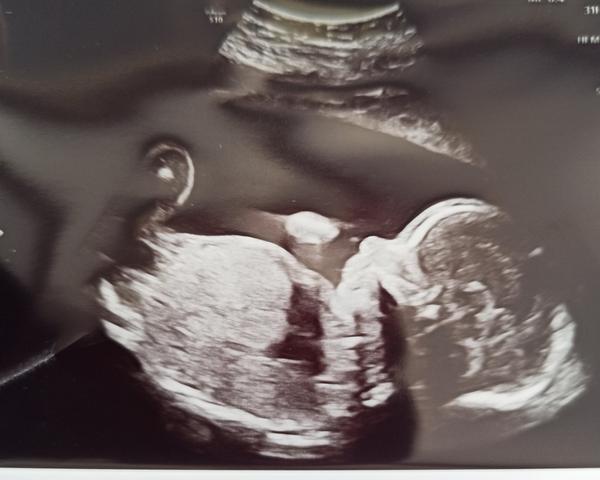

Máme po 2 screeningu 😊 máme potvrzenou holčičku ❤️❤️ Má 340g a je v pořádku 🌸🌸